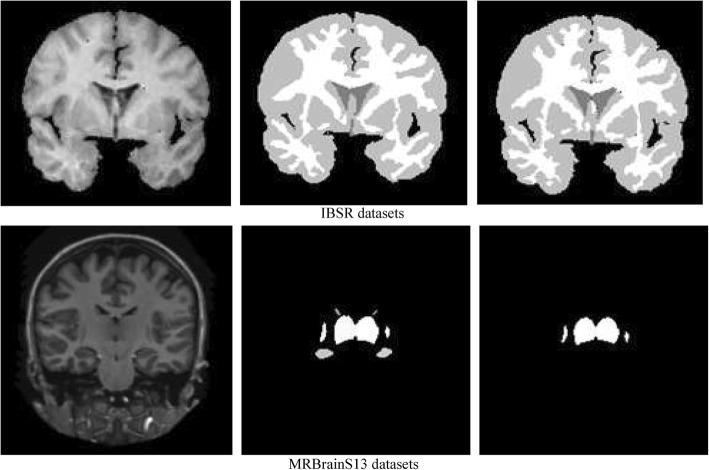

RESULTS

The proposed method was applied to the challenging publicly available MR datasets IBSR and MRBrainS13. In the MRBrainS13 datasets, we obtained an average thalamus Dice similarity coefficient of 0.927 ± 0.014 and an average Hausdorff distance (HD) of 2.92 ± 0.53. In the IBSR datasets, we obtained a white matter (WM) average Dice similarity coefficient of 0.827 ± 0.04 and a gray gray matter (GM) average Dice similarity coefficient of 0.853 ± 0.03.